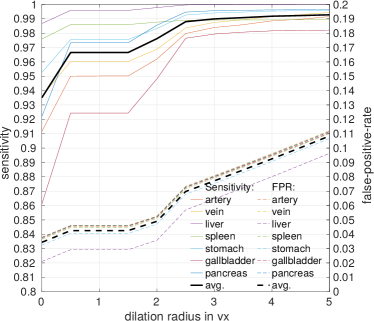

In the first stage, we apply simple thresholding in combination with morphological operations (hole filling and largest component selection) to get a mask of the patient’s body in a slice-by-slice fashion. This mask can be utilized as candidate region to reduce the number of voxels necessary to compute the network’s loss function and reduce the amount of input 3D regions shown to the CNN during training to about 40%. After training, the first-stage FCN is applied to each image to generate candidate regions for training the second-stage FCN (Fig. 3). We define the organ labels in the testing phase using the of the class probability maps. Any foreground label is then dilated in 3D using a voxel radius of . We compare the recall and false-positive rates of this first-stage FCN with respect to for both the training and validation sets in Fig. 2. gives good trade-off between high recall (99%) and low false-positive rates for each organ on our training and validation sets.